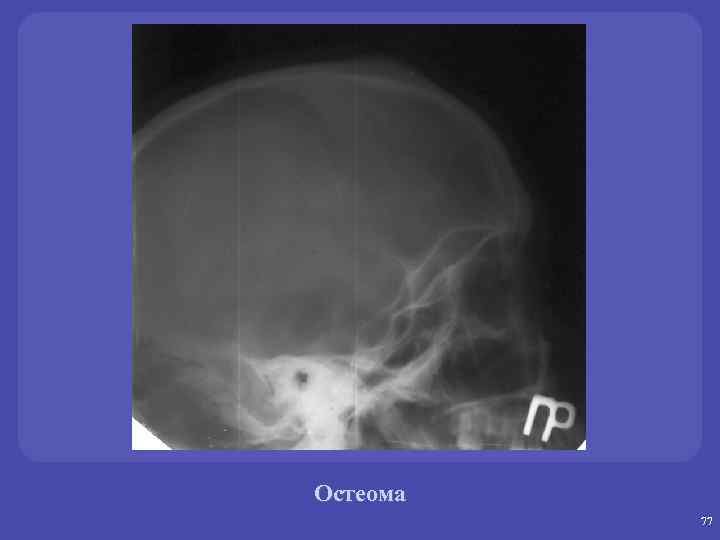

ОСТЕОМА – локализация: кости свода черепа, воздухоносные пазухи черепа ОСТЕОБЛАСТОКЛАСТОМА – локализация: метаэпифизы ХОНДРОМА – локализация: метадиафиз трубчатых костей ОСТЕОХОНДРОМА – локализация: метадиафиз трубчатых костей и плоские кости 75

Остеома. Локализация. üкости свода черепа, воздухоносные пазухи черепа (компактная) üКости стопы, кистей, длинные трубчатые кости (губчатая). üЧаще краевая, эндостальная локализация – крайне редко.

Остеома 77